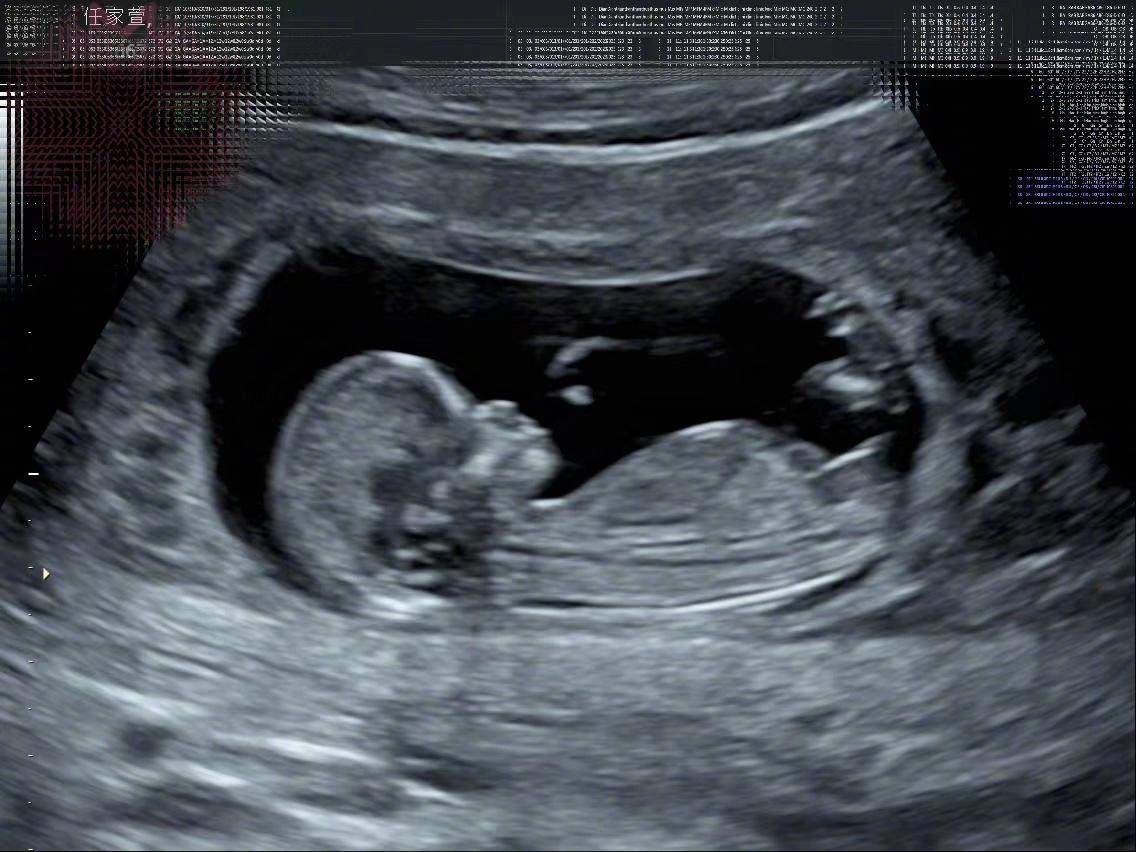

3月13日,台湾艺人、S.H.E组合成员任家萱Selina在微博宣布怀孕,她表示:“真心感谢,满心喜悦,跟大家分享一个好消息。我~怀~孕~了!肚子里的宝贝,我取名叫‘小腰果’……我说:‘腰果啊~弯弯的,似微笑的眼睛。上扬的、似笑开的嘴角!’妈妈希望腰果是个快乐的小孩。”

Selina透露,目前怀孕12周,自己先前熬夜跨完年觉得身体不舒服,隔几天想说测一下,结果立刻出现两条线,瞬间觉得“我要当妈妈了,真的就哭了”。她还给孩子写了一首诗:“去年三月,我介绍小徐(男友)时写了首打油诗,公平起见,今年这首打油诗就送给小腰果吧!女人四一一枝花,幸运生命正萌芽,彼此珍惜同步伐,大喜大乐请吃糖。春暖花开,我的腰果也来了。”

41岁Selina任家萱宣布怀孕,与小7岁男友备孕半年得偿心愿 “小腰果”照片